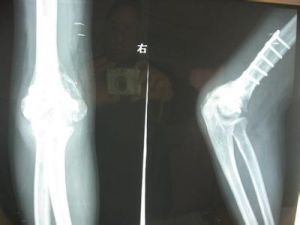

檢查

用於本病的檢查方法主要是X線檢查,且不同型別具有不同的表現: 1.初期型X線檢查表明在初期不形成典型的骨化,但可顯示軟組織內不規則棉絮模糊陰影。 2.成熟型肘關節損傷後已形成骨化或初期骨化已硬化,X片可顯示邊緣光滑之骨質密度樣陰影,陰影範圍較前縮小而集中。

有明確外傷史;傷後反覆被動屈伸關節;關節腫脹、疼痛持續不消伴局部溫度升高;關節活動範圍逐漸變小;X線早期無特殊,3~4周后關節周圍發現雲霧狀的骨化團,晚期骨化範圍縮小,密度增高,界限清楚。一般傷後3~6周內有增大趨勢,6~8周后趨於穩定。